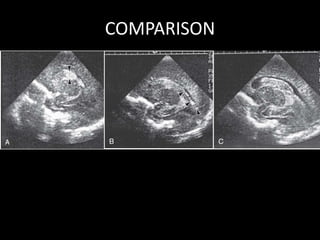

A, Grade I: Note the echogenic blood in the germinal matrix (arrowheads)

just anterior to the anterior tip of the choroid plexus, which (normally) is

also echogenic.

B, Grade II: Note the echogenic blood

(arrowheads) filling <50% of the ventricular area.

C, Grade III: Note the large blood clot nearly completely

filling and distending the entire lateral ventricle

COMPARISON